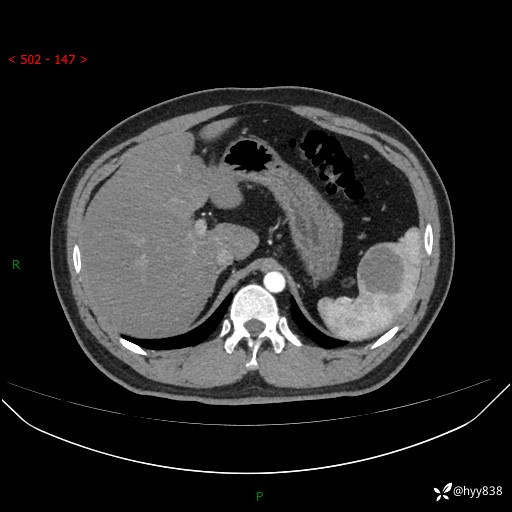

【患者信息】:31岁/男

【主诉】:超声发现脾脏肿物,为进一步诊治来我院,门诊以“脾脏占位”收入院

【检查】:上腹部CT平扫+增强